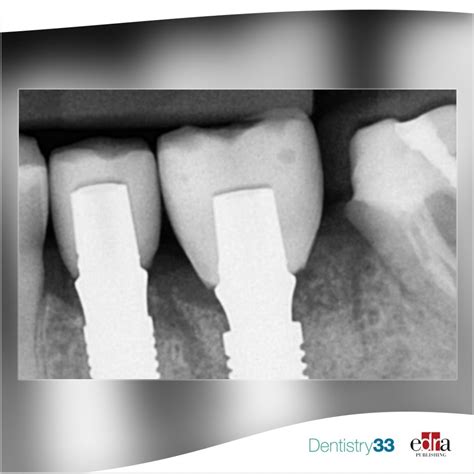

• Dental Implants: Crown X Ray Dental technology helps in planning the placement of dental implants by providing a detailed view of the jawbone and surrounding tissues.